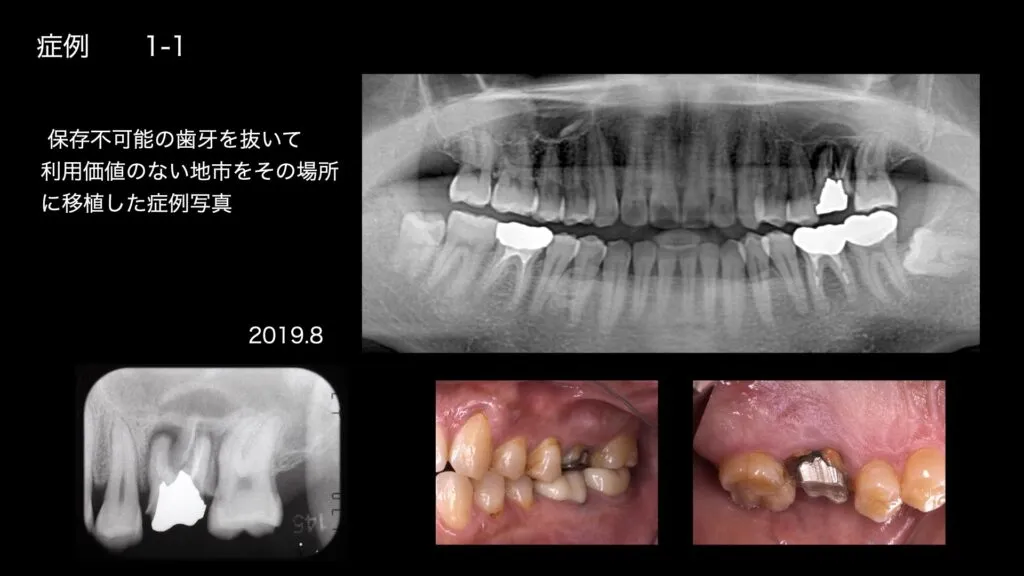

「歯の移植」という選択肢

ご自身の余っている歯を抜いて、失ったところへ埋める治療を歯の移植と言います。最も多いのは、奥歯を抜かなければならなくなった時に、親知らずを使うというケースです。また、歯並びが悪く1本の歯が歯並びから飛び出た位置にある場合は、その歯を使うこともあります。一般的には歯の移植が成功する(根がきちんと骨と結びつく)可能性は9割程度だと言われていますが、当院では高い確率で成功しています。それは、歯の根っこの部分が細菌感染しないよう、細心の注意を払いながら治療を進めているからです。歯を抜くことになったが入れ歯やインプラントは避けたい…そんな方は、当院で歯の移植の可能性をご相談いただければと思います。